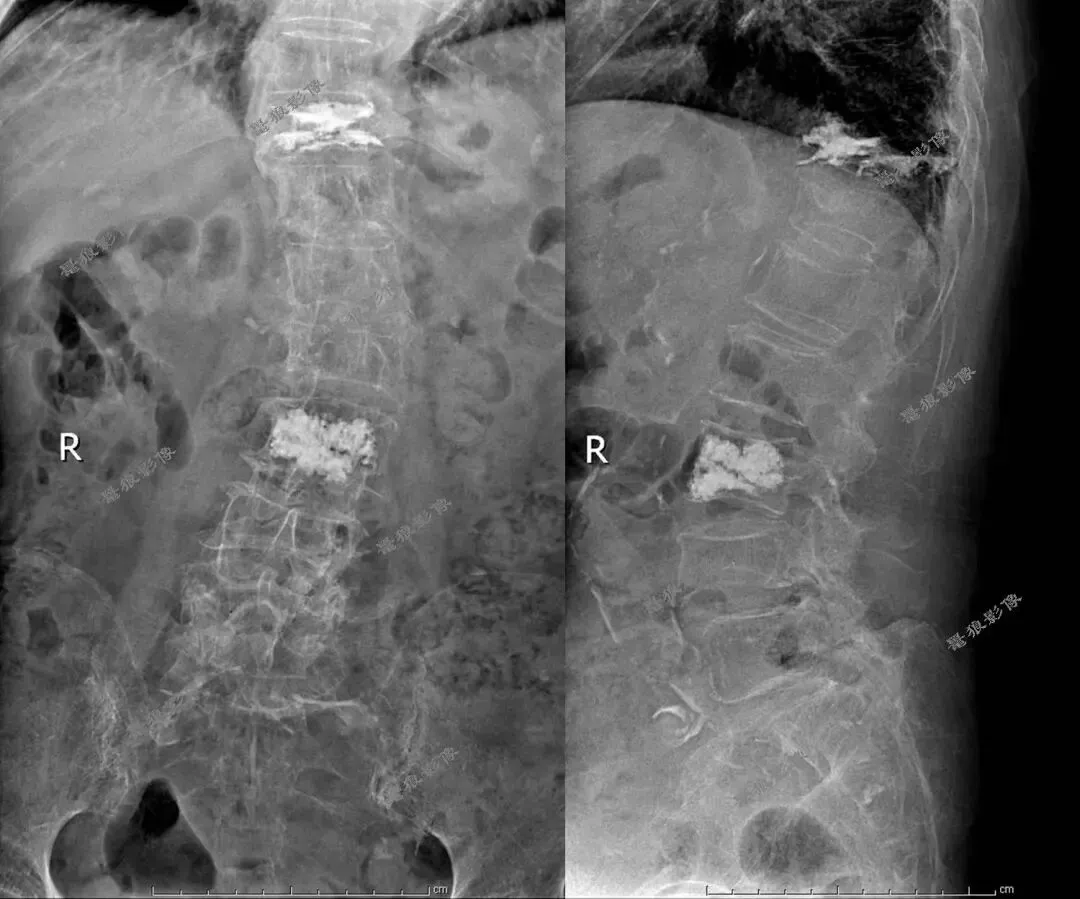

一、腰椎平片(术前)

考虑腹主动脉下段动脉瘤并附壁血栓。